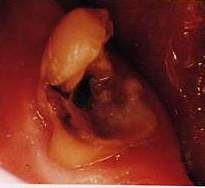

Buongiorno a tutti. Ieri mangiando un banalissimo grissino mi è saltata un'otturazione su un molare. A quanto pare l'area interessata sembra di dimensioni piuttosto grandi, ma potrebbe essere solo un'impressione. Il dente è bianco e al momento non mi fa alcun male, solo un modesto aumento della sensibilità al caldo e al freddo. Volevo chiedervi se, secondo voi, potrebbe essere necessario devitalizzare il dente, oppure se potrebbe essere sufficiente, visto che non ho dolore rifare l'otturazione. Ringrazio per la cortese attenzione.

Caro Massimiliano dipende, se la frattura è eccessivamente estesa e la carie che ha sottominato l'otturazione è arrivata in polpa può anche darsi, tuttavia ricorda che la lingua è una delle parti con sensibilità tattile maggiore del nostro corpo quindi una mancanza piccola può sembrarti una voragine vai dal dentista al più presto e vedrai che basterà una otturazione distinti saluti